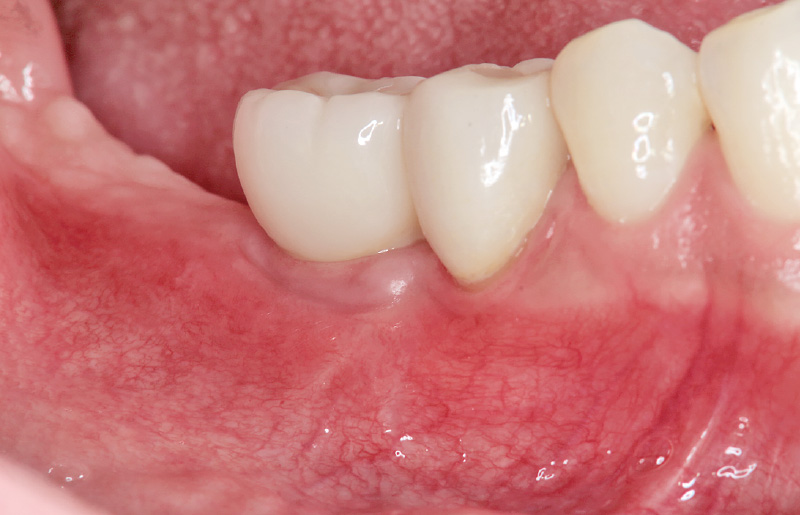

症例1:インプラント周囲炎(図1~8)

•患者:50歳男性、喫煙者、リウマチにてメトトレキサート内服

•経過:3年前、6部にGBR併用でインプラント埋入

•所見:頰側に骨欠損を伴うインプラント周囲炎を認めた

•考察:喫煙および免疫抑制剤の影響が要因と考えられる

図1 症例1:6のインプラント周囲炎にてBOP(+)排膿を認める。 -